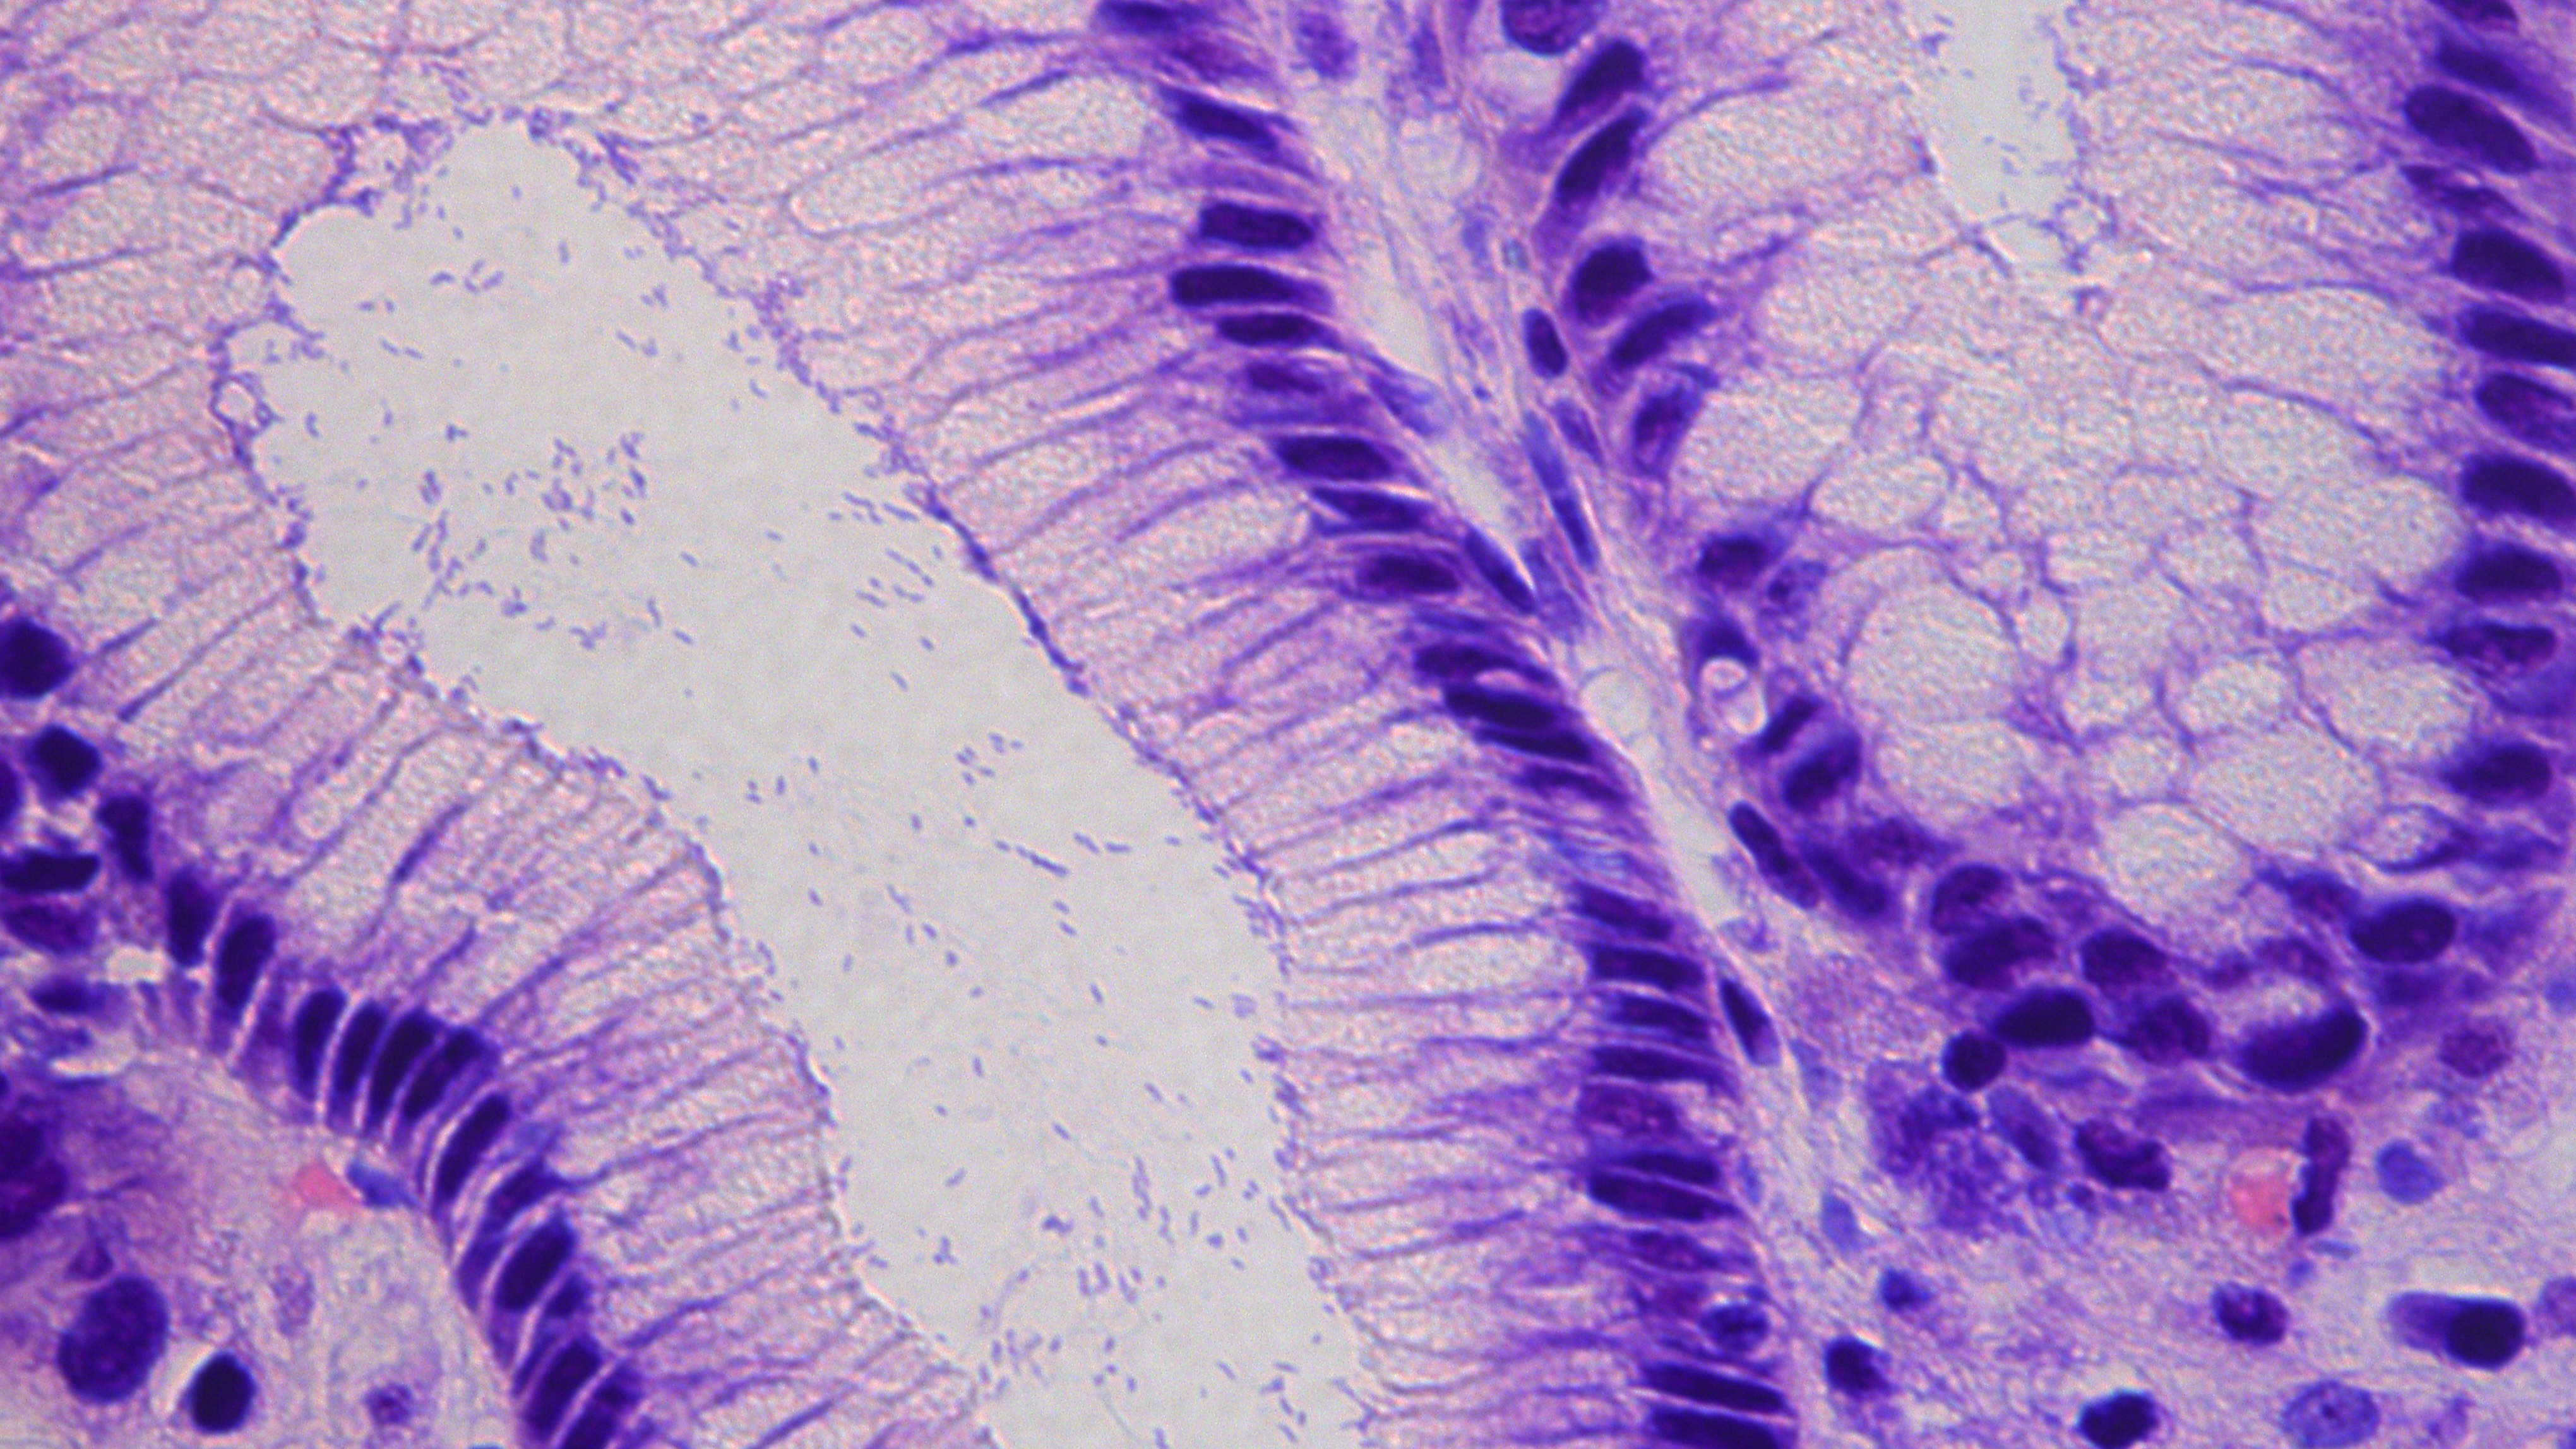

Darmregeneration nach Krebstherapie

Regensburg, 27.11.2025